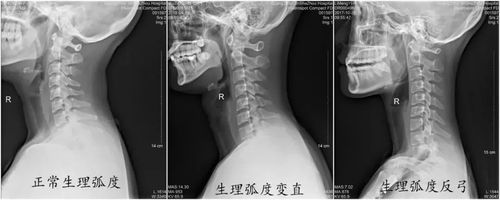

颈椎生理曲线图

颈椎生理曲线图,脊柱的生理曲线图

颈椎生理曲度

颈椎生理曲度变直

颈椎正常生理曲度图片

生理曲度